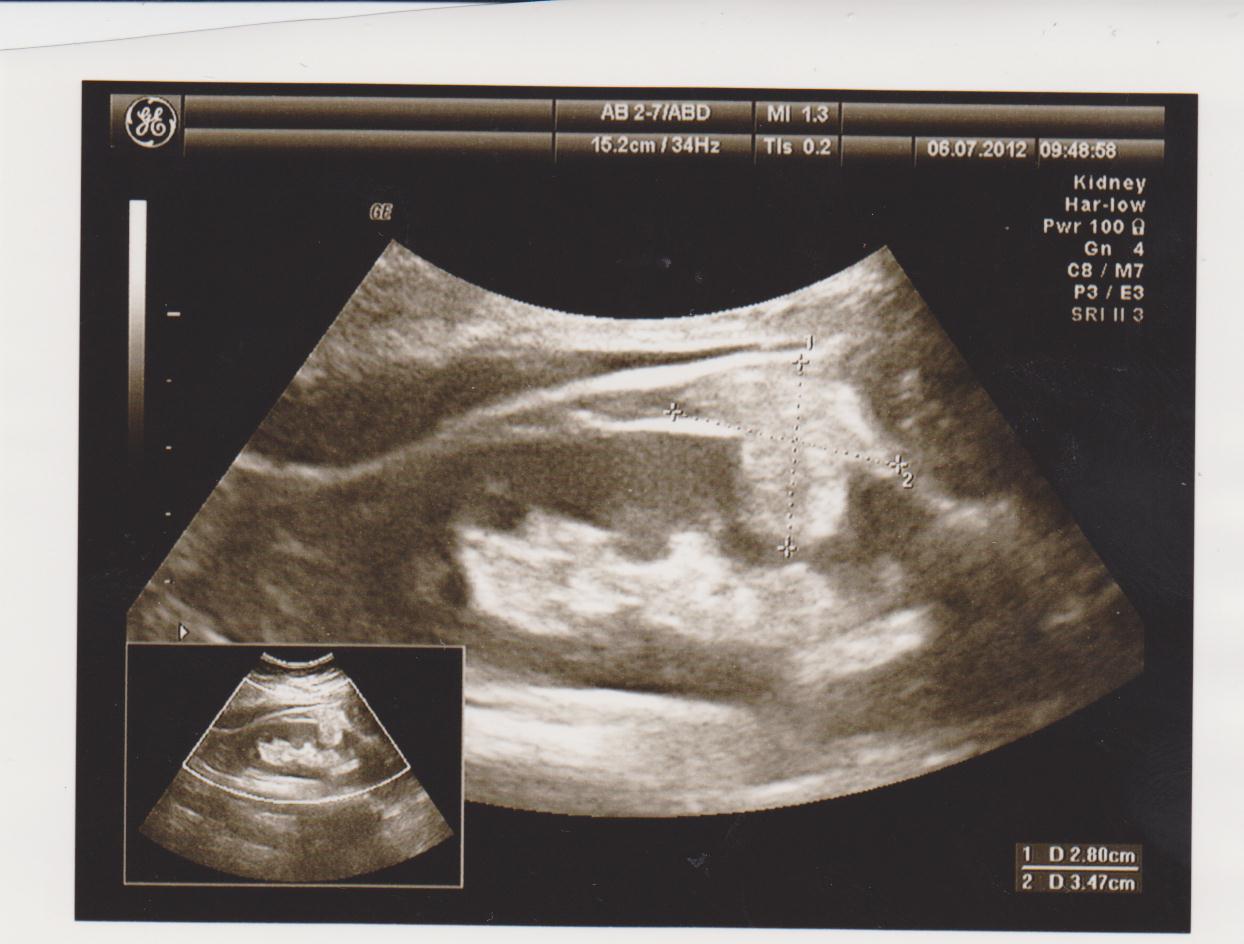

Частые болезни: кисты, новообразования (ангиомиолипомы, гемангиомы, фибромы…), конкременты (камни), расширение мочевых путей (расширение лоханки или чашечек — пиелоэктазия, гидронефроз), хроническое воспаление (пиелонефрит), смещение почек (опущение — нефроптоз, нахождение в нетипичном месте — дистопии), удвоение почки, рак почки…

Ниже я привел пару УЗИ снимков из практики, все они есть в галерее УЗИ на сайте, смотрите и не пугайтесь: